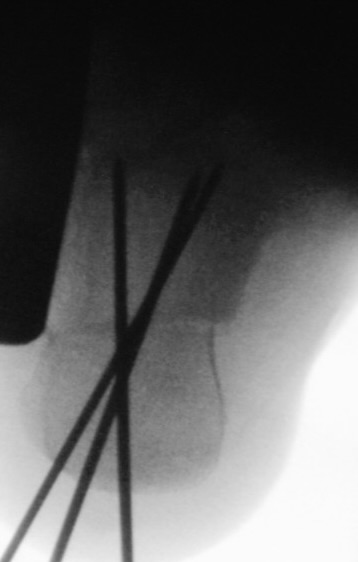

Zusätzlich schränken Wachstumsfugen die Wahl der Osteosynthese ein. Eine die Fuge kreuzende Osteosynthese ist ausschließlich mit Kirschner-Drähten möglich (Abb. 3).

Abb. 3 a-j: Beispiel einer Calcaneusverschiebeosteotomie mit offenen Wachstumsfugen und der entsprechenden Osteosynthese mit Kirschner Drähten. Lokalisation der Osteotomie (a), Lage der Fräse (b-d), Drahtlage mehrere Ansichten (e-h), Heilung der Osteotomie 4 Wochen postoperativ und Entfernung der Drähte (i-j).